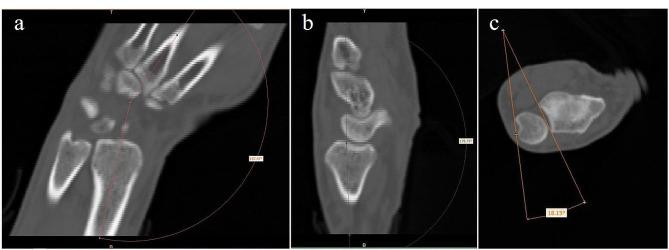

Eight volunteers were recruited to accept CT scans in six extreme wrist positions. The images of DICOM mode were imput into the Mimics analytical system, the segmented scaphoid, lunate and radius were exported in mode of ASCII STL and were opened in the software of Geomagic studio. We created four planes based on anatomic markers on the surface of the radius and scaphoid to confine the proximal scaphoid to form the so-called non-contact regions. We measured and compared the areas in six targeted positions.

RESULTS

Amidst six extreme wrist positions, area of the non-contact region in extreme dorsal extension (59.81 ± 26.46 mm) was significantly the smallest, and it in extreme palmar flexion significantly was largest (170.51 ± 30.44 mm). The non-contact regions increased in order of dorsal extension, supination, ulnar deviation, radial deviation, pronation and palmar flexion. As for two-group comparison, the non-contact region showed significantly larger (p < 0.05) in palmar flexion than the others except for in pronation individually, and in radial deviation (p < 0.05) than in dorsal extension.

招募了 8 名志愿者进行 6 种极端腕关节位置的 CT 扫描。DICOM 模式的图像被输入 Mimics 分析系统,以 ASCII STL 模式导出分割的舟状骨、月骨和桡骨,并在 Geomagic Studio 软件中打开。我们基于桡骨和舟状骨表面的解剖标记创建了四个平面,以限制近侧舟状骨形成所谓的非接触区。我们测量并比较了 6 个目标位置的面积。

结果

在 6 种极端腕关节位置中,极度背伸位(59.81±26.46mm)的非接触区最小,极度掌屈位(170.51±30.44mm)最大。非接触区依次为背伸、旋前、尺偏、桡偏、旋前和掌屈增加。对于两组比较,除了单独的旋前位外,掌屈位的非接触区明显大于其他位置(p<0.05),桡偏位的非接触区也明显大于背伸位(p<0.05)。